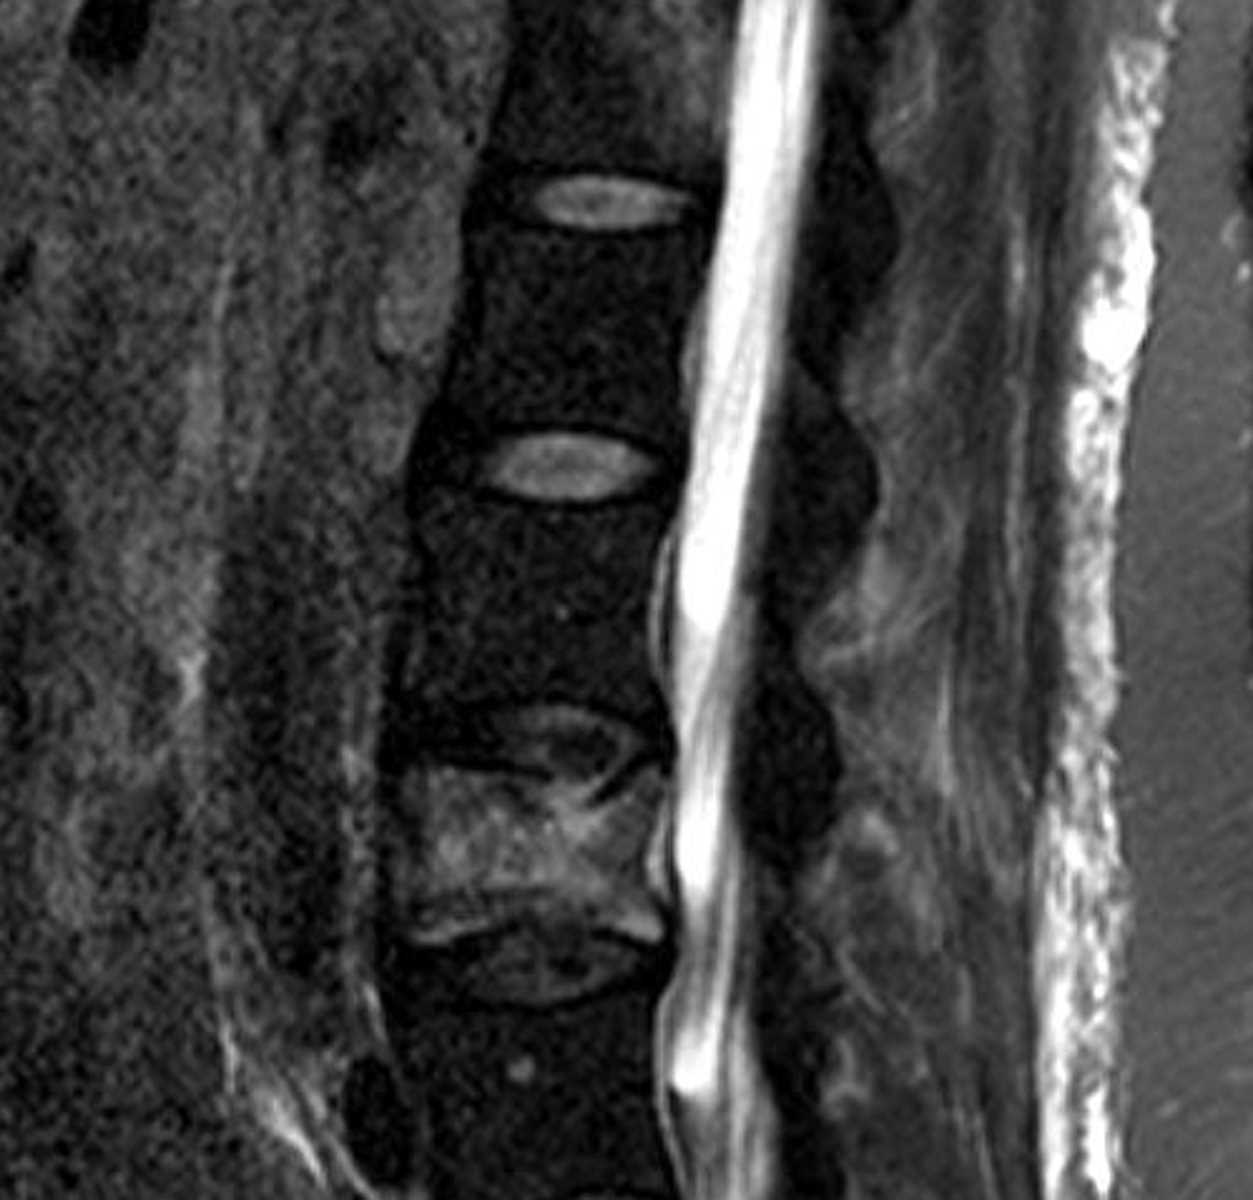

Venolymphatic Malformation

There is a lobulated, multilocated T2 hyperintense mass in the left parotid space extending to the submandibular region. There is some associated enhancement with several prominent associated vessels, but the majority of the lesion does not enhance. This is most consistent with a venolymphatic malformation.